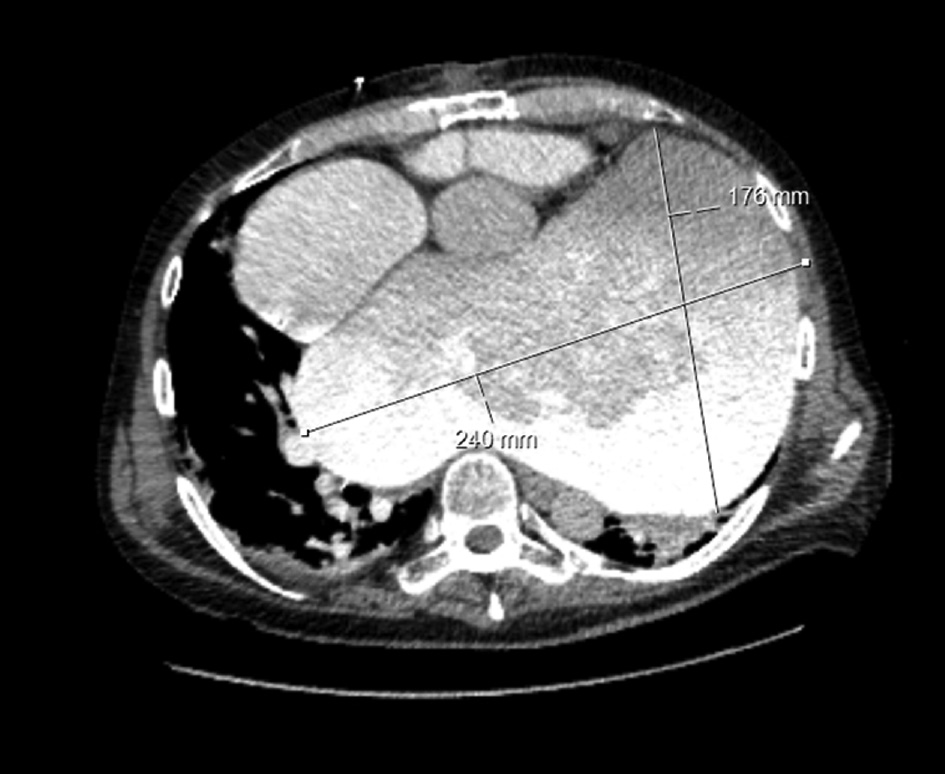

A 57-year-old male with acute heart failure was admitted to a community hospital after return of spontaneous circulation (ROSC) following cardiac arrest and approximately 65 min of out-of-hospital CPR. Although his cardiac rhythm at the time of ROSC was not documented, he was in atrial fibrillation upon arrival at the community hospital. It turned out that he had undergone redo mitral valve replacement with a mechanical valve and tricuspid valve repair 5 years preceding the event. Nearly two decades earlier, he had undergone mitral valve replacement for mitral regurgitation in the setting of cardiomegaly. Echocardiography (ECG) and computed tomography (CT) showed a grotesque case of GLA (Figures 1 and 2 ) that had gone undiagnosed because the patient had not presented for follow-up examinations after the most recent surgical procedure (i.e. for 5 years). ECG findings included sludge in GLA and a left ventricular ejection fraction of 10%. Fluoroscopy showed a normal motion of mitral valve leaflets.

Transversal section of GLA on initial CT after cardiac arrest and CPR (dimensions: 240×176 mm).